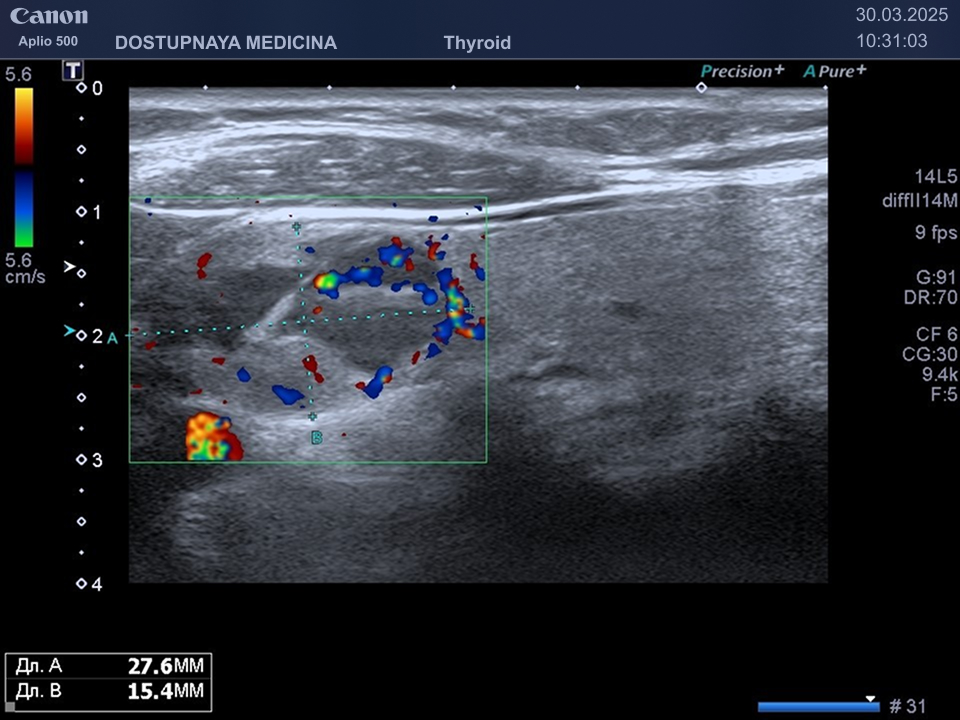

В ультразвуковой диагностике существует классификация образований щитовидной желзы по TIRADS, которая по различным критериям определяет степень онкоопастности того или ионого узла. При оценке учитывается эхоструткура образования ( кистозная, губчатая, солидная или солидно-кистозная), эхогенность ( анэхогенное, гиперэхогенное, гипоэхогенное), пространственная ориентация горизонтальная, вертикальная, неопределённая), контуры образования (ровные, дольчатые, зазубренные с острыми углами), наличие эхогенных включений( макрокальцинаты, микрокальцинаты, периферическая кольцевидная кальцификация). В зависимости от этих критериев выделяют различные категориии объёмных образований в щитовидной железе:

TIRADS 4 – умеренно подозрительное образование, требующие динамическое наблюдение и тонкоигольной биопсии при размерах узла больше 1.5 см.

TIRADS 5 – высоко подозрительное образование, требующие динамическое наблюдение и тонкоигольной биопсии при размерах узла больше 1 см.

При подозрении на озлокачествление и увеличении узла в размерах требуется тонкоигольная пункционная биопсия с полседующим цитологическим исследованием, полученного материала.